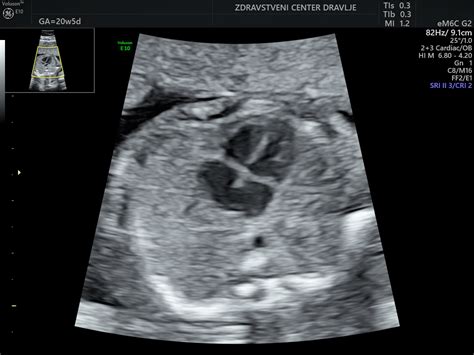

Pri nosečnicah, ki pričakujejo dvojčka, je rast obeh otrok do tega tedna običajno enaka, vendar se lahko med 30. in 32. tednom nekoliko upočasni. Ginekolog lahko v tem času naroči biofizični profil ploda, ki vključuje ultrazvok in nestresni test (NST). NST s senzorji na trebuhu spremlja popadke in srčni utrip dojenčka ter preverja, kako se srčni utrip odziva na gibanje otroka.

Med zadnjim ultrazvočnim pregledom pred porodom je pomembno določiti položaj posteljice. Če posteljica delno ali v celoti prekriva maternično ustje (predležeča posteljica ali placenta previa), je lahko potreben porod s carskim rezom. Čeprav so tehnike carskega reza napredovale, ostaja to operacija, ki zahteva anestezijo in okrevanje.